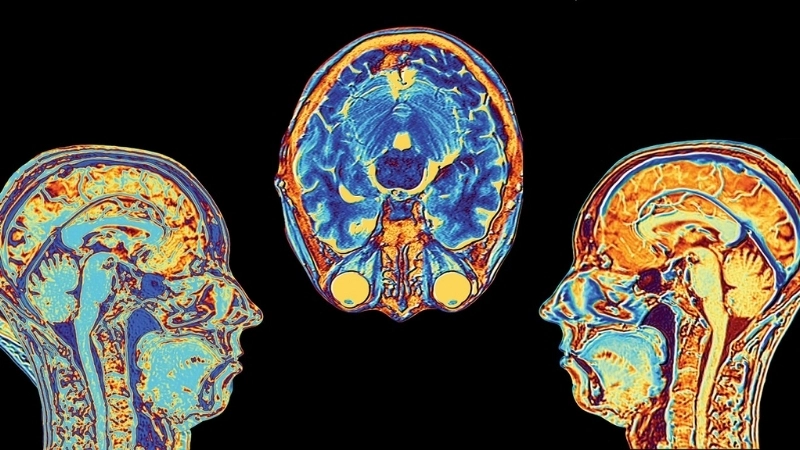

Mọi chuyện bắt đầu từ não bộ, trung tâm chỉ huy của cơ thể. Khi bạn đối mặt với một tình huống được cho là mối đe dọa, bất công hoặc khó chịu, một vùng não nhỏ có tên là hạch hạnh nhân (amygdala) sẽ được kích hoạt.

Hãy tưởng tượng hạch hạnh nhân như một hệ thống cảnh báo sớm. Nó không cần suy nghĩ logic mà phản ứng ngay lập tức, gửi tín hiệu khẩn cấp đến các bộ phận khác của não. Đây là lý do vì sao cơn giận có thể bùng lên trước khi bạn kịp nhận thức điều gì đang xảy ra.

Não bộ là trung tâm điều khiển mọi cảm xúc của con người